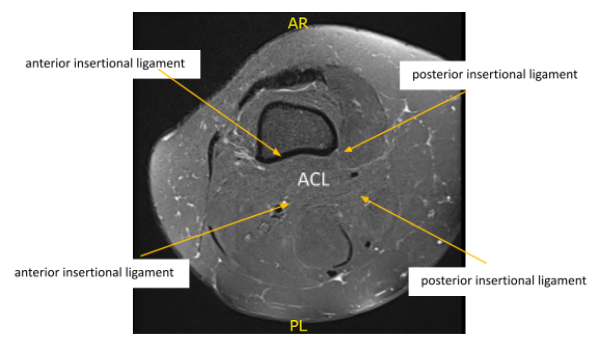

MRI reviewed. There is mild mucinous transformation of the ACL. is a longitudinal tear the posterior horn of the medial meniscus extending into the posterior root attachment site. See series 5 images 19-21. A small joint effusion is noted and mild patellar cartilage wear.